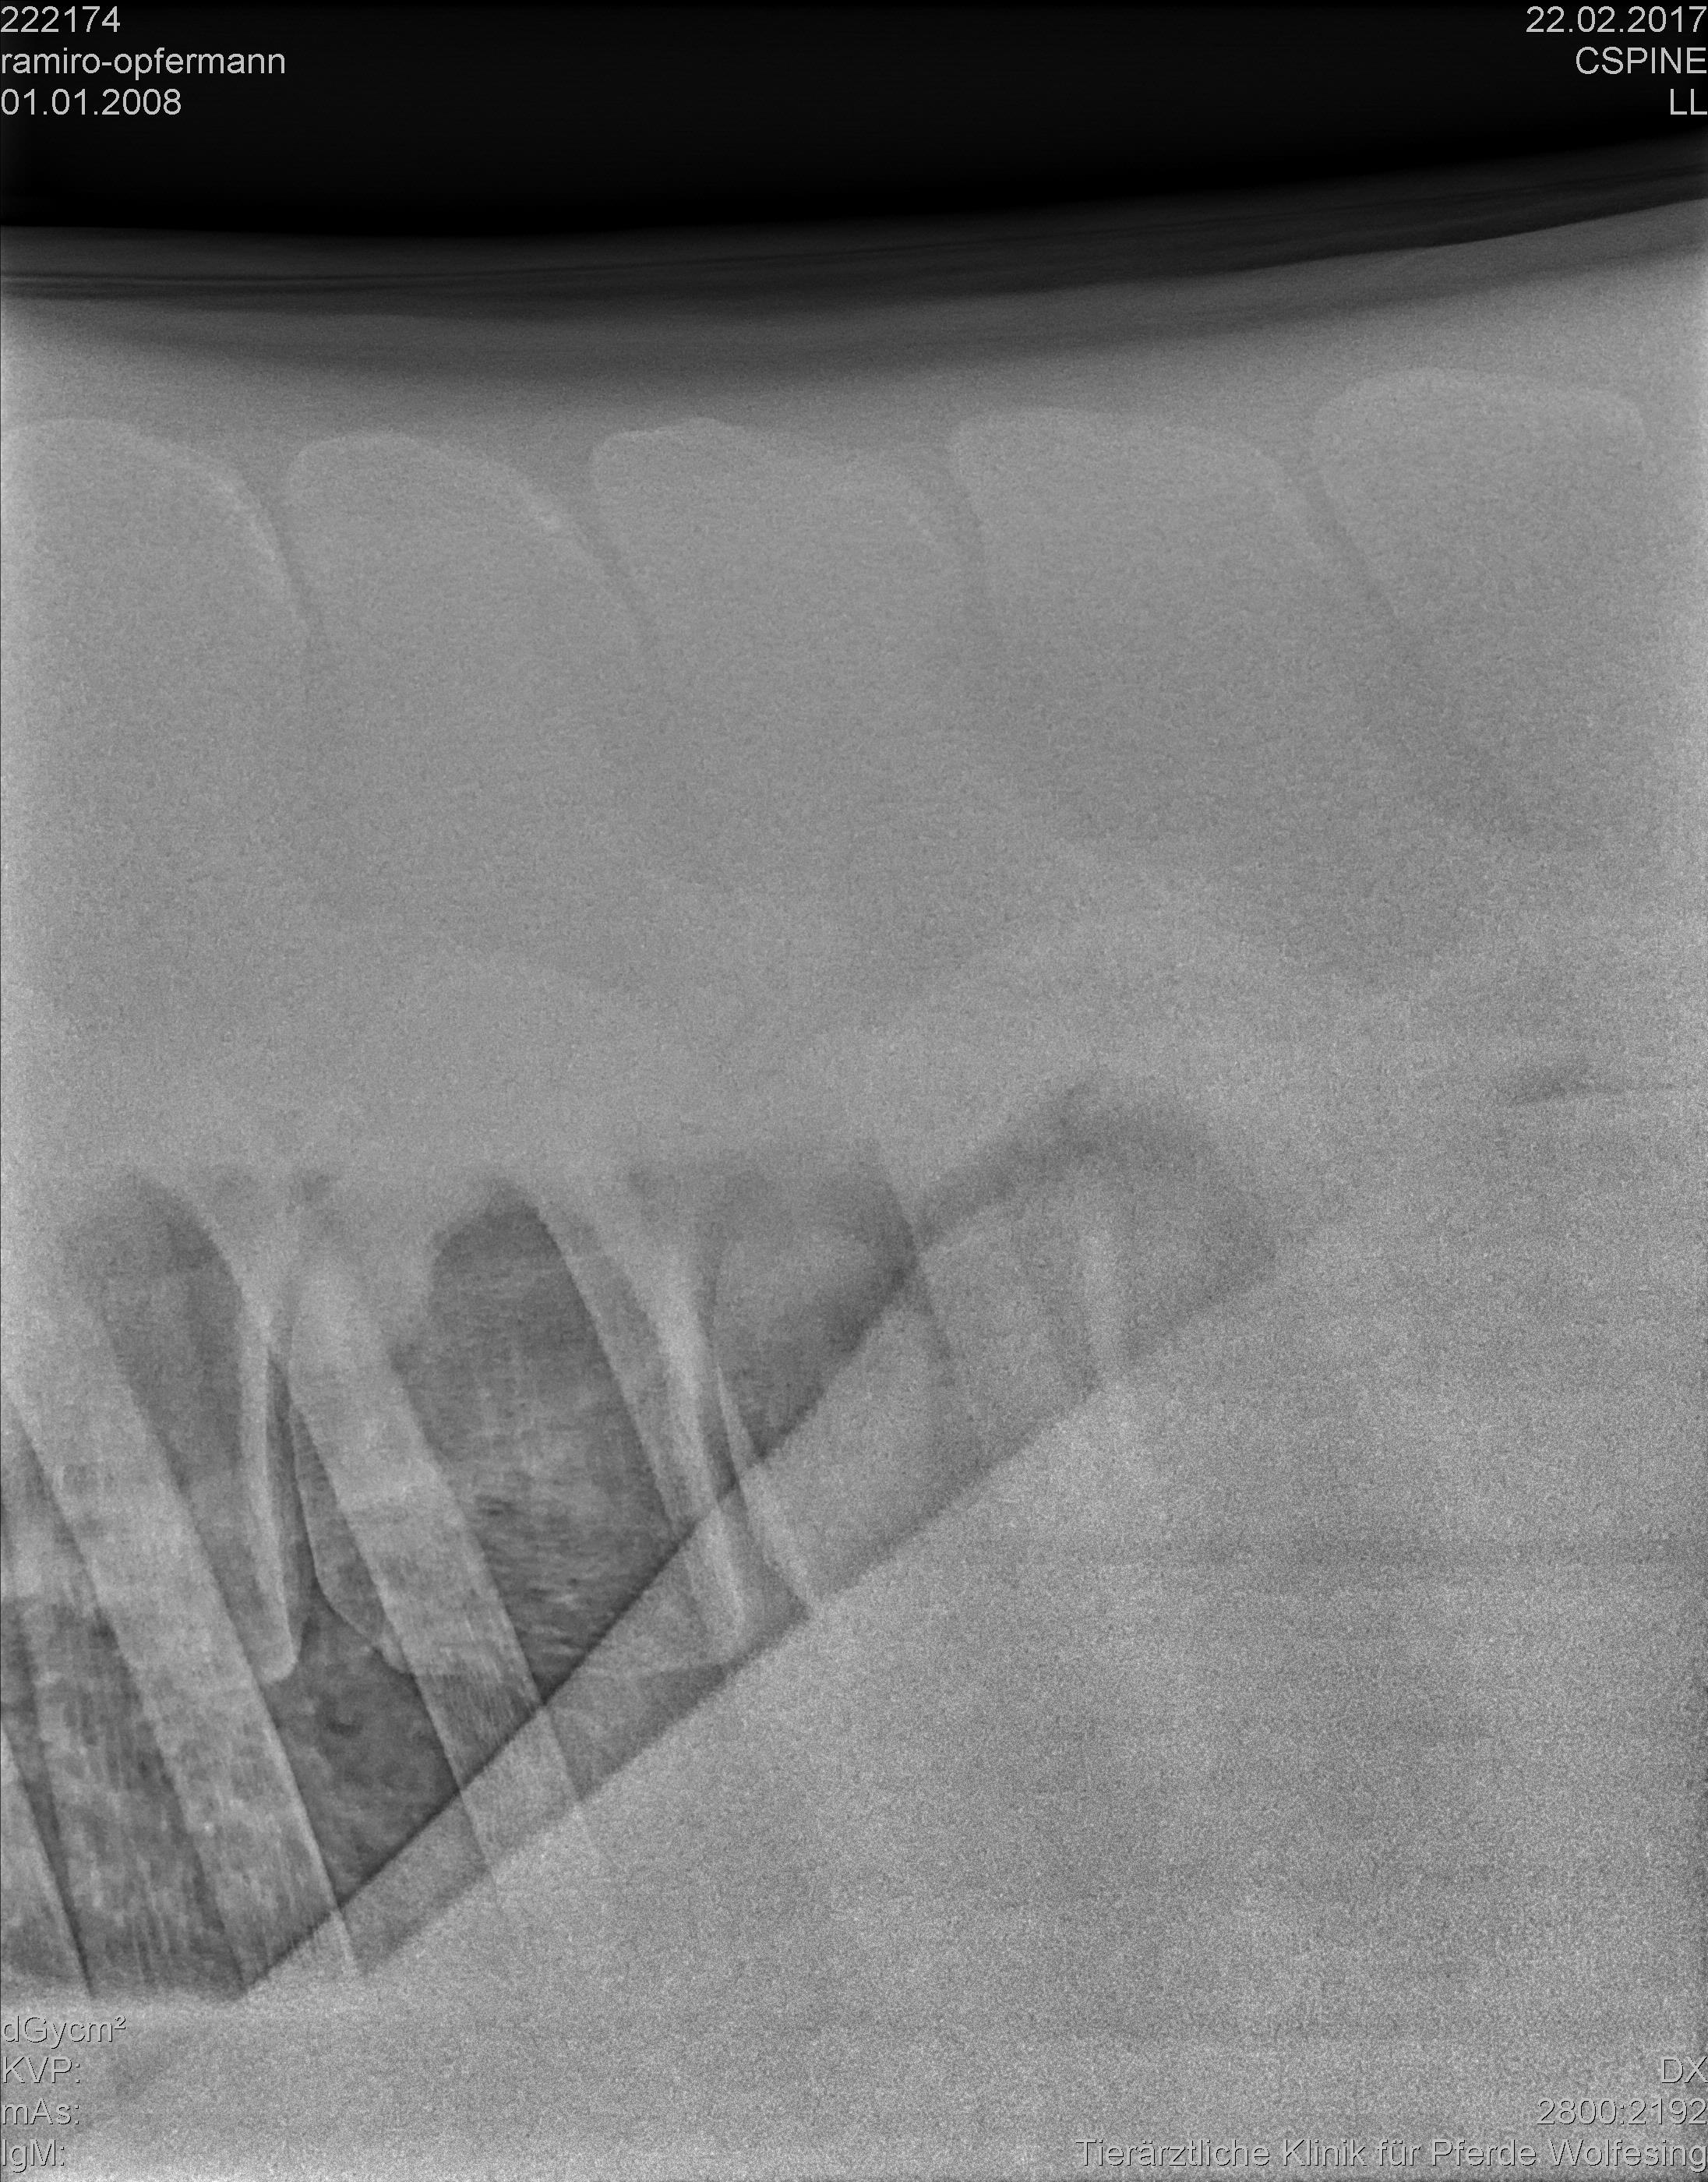

хочу обратиться за помощью, советом и также, возможно, обменяться опытом с владельцами лошадей с подобным диагнозом. А именно – у моей лошади диагноз Kissing Spines.

К моменту постановки диагноза лошадь находилась в моем владении только 3 недели (дата покупки 29.01.2017, дата постановки диагноза – 22.02.2017), т.е. я купила ее уже с этим диагнозом, не зная этого. Рентгены приложила.